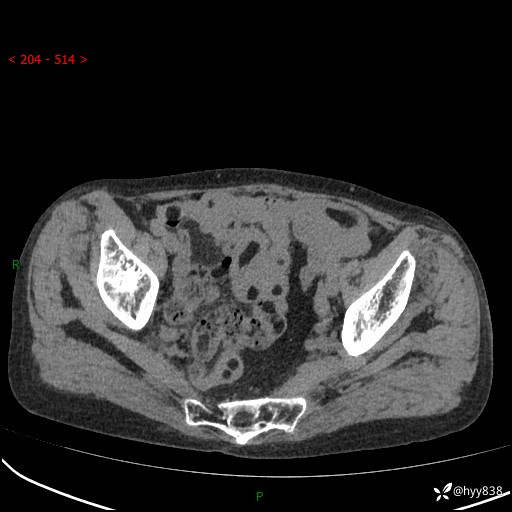

全腹部CT平扫